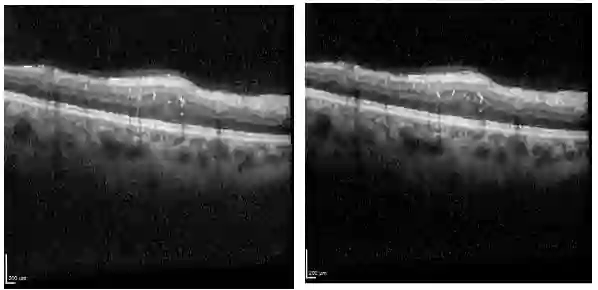

Ophthalmic diseases represent a significant global health issue, necessitating the use of advanced precise diagnostic tools. Optical Coherence Tomography (OCT) imagery which offers high-resolution cross-sectional images of the retina has become a pivotal imaging modality in ophthalmology. Traditionally physicians have manually detected various diseases and biomarkers from such diagnostic imagery. In recent times, deep learning techniques have been extensively used for medical diagnostic tasks enabling fast and precise diagnosis. This paper presents a novel approach for ophthalmic biomarker detection using an ensemble of Convolutional Neural Network (CNN) and Vision Transformer. While CNNs are good for feature extraction within the local context of the image, transformers are known for their ability to extract features from the global context of the image. Using an ensemble of both techniques allows us to harness the best of both worlds. Our method has been implemented on the OLIVES dataset to detect 6 major biomarkers from the OCT images and shows significant improvement of the macro averaged F1 score on the dataset.